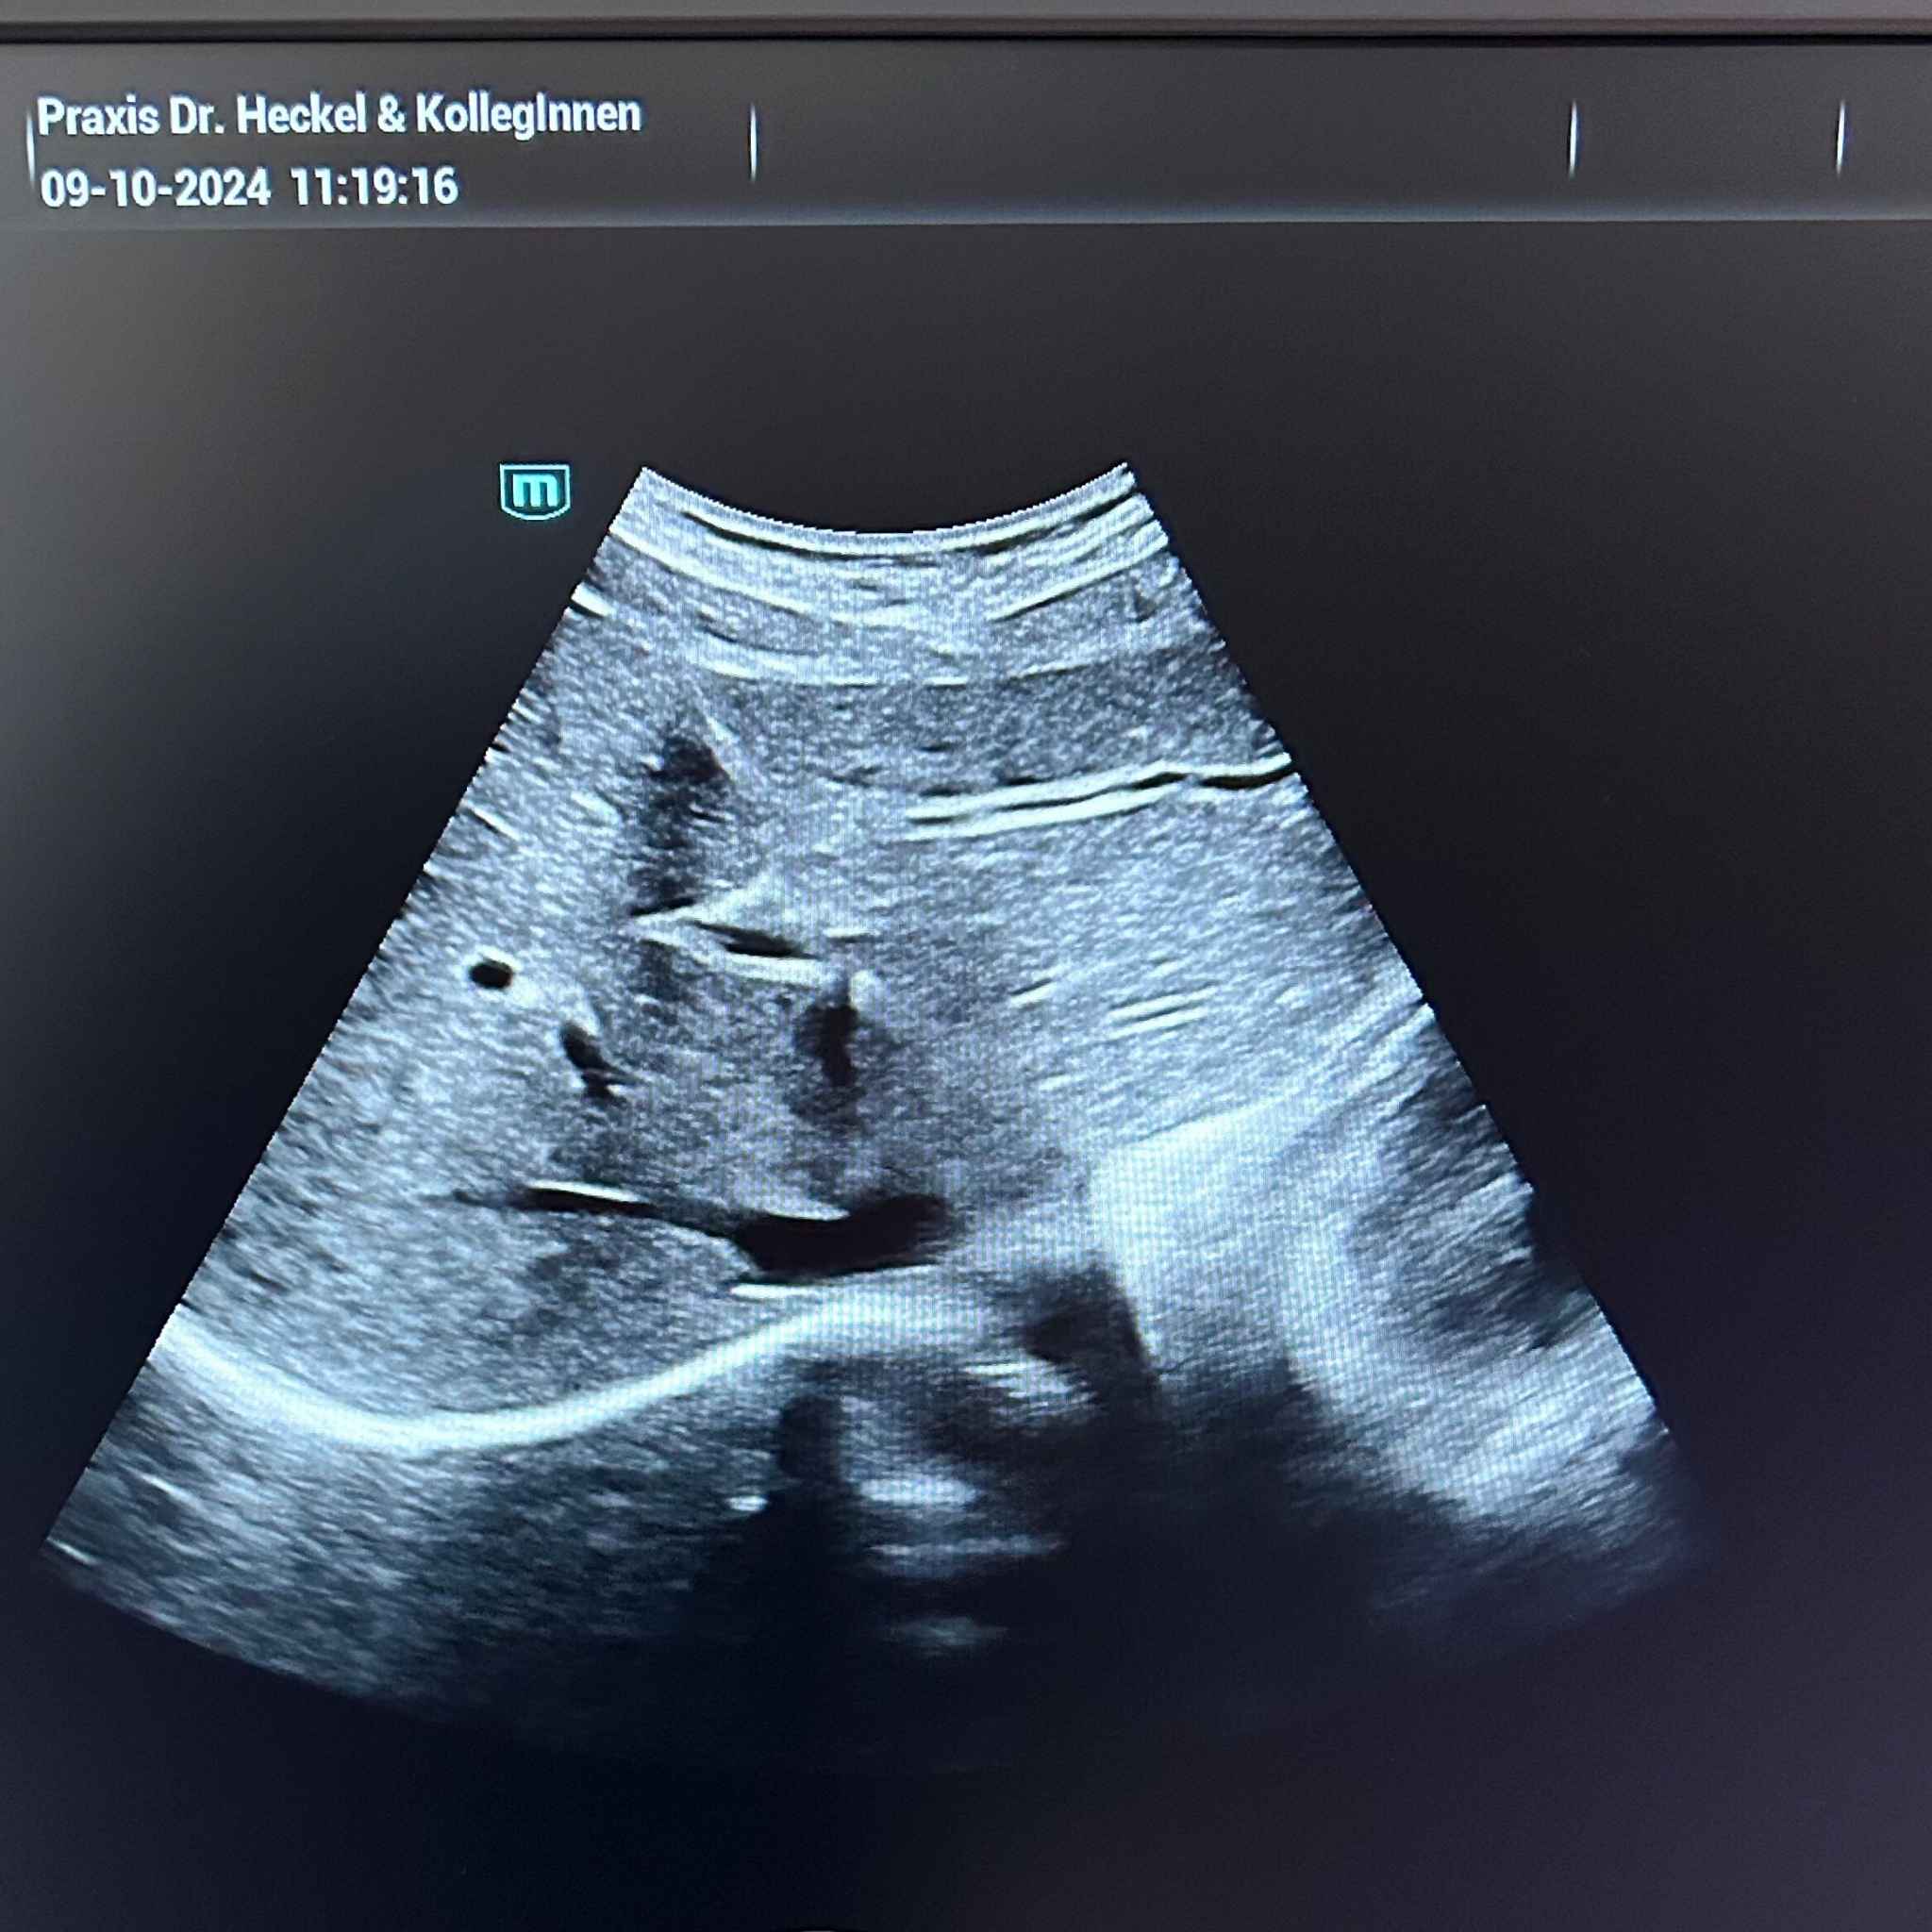

Ultraschalluntersuchungen